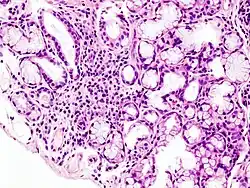

![]() Histopatologiczny obraz miejscowego nacieku limfatycznego w mniejszej śliniance powiązany z zespołem Sjögrena | |

- nacieki zapalne z limfocytów w badaniu histologicznym.

W obrazie histologicznym bioptatu z wargi dolnej stwierdza się nacieki zapalne i obecność komórek plazmatycznych.